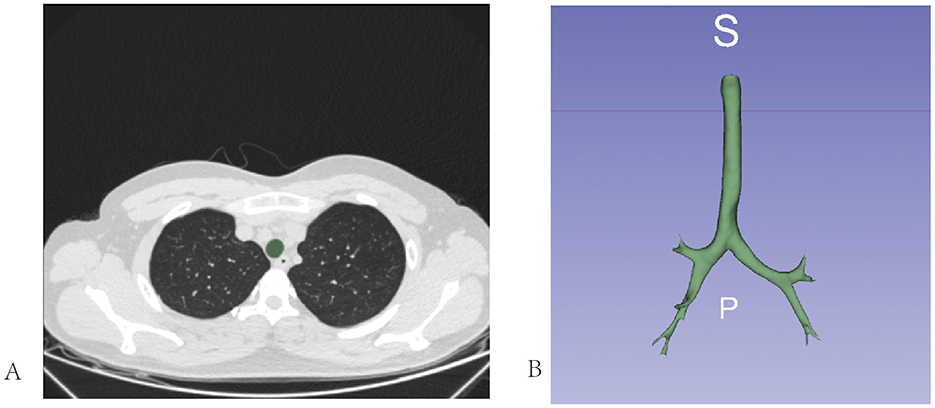

Delineating the region of interest (ROI)

The region of interest (ROI), a designated image area marked within an image, served as the primary focus of subsequent analyses. Further in-depth analytical processing could be conducted by fixing this region. In this study, the ROI was localized within the mid-airway structures of the tracheobronchial tree. Specifically, it encompassed the entire segment of the tracheal lumen from the inferior border of the cricoid cartilage to the carina, as well as the proximal portions of both the main bronchi.

We employed a semi-automatic approach using 3DSlicer 4.11 (17) to delineate the ROI. The detailed steps are as follows.

(1) We initiated the drawing process at the subglottic cricoid cartilage level using a level-tracing tool. This tool allows the generation of a contour within a plane by moving the mouse; all pixels on this contour share the same grayscale value as the pixel at the location of the mouse. Five consecutive planes were drawn in this manner (Figure 4A).

(2) Subsequently, we used the Fast Marching module within the SegmentEditorExtraEffects plugin to fill the drawn planes. We set the maximum parameter to 1% and selected a segment volume within a range of 3%−10%.

Following these steps, a three-dimensional ROI of the subglottic tracheal and bronchial airways was constructed (Figure 4B).